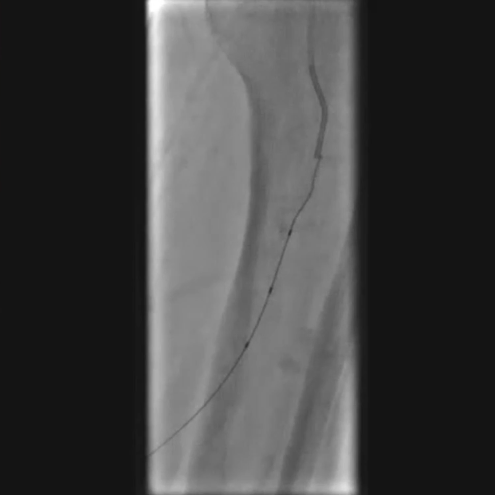

铁基可降解支架植入

按计划植入3×38mm载药铁基可降解支架,准确定位以完全覆盖病变;采用8 atm压力球囊扩张释放支架,确保支架充分张开。

术后评估

造影显示:胫腓干动脉血流恢复通畅,支架形态及位置理想,胫后动脉显影较术前明显改善;

腔内超声证实:铁支架完全张开、贴壁良好,无明显残余狭窄。